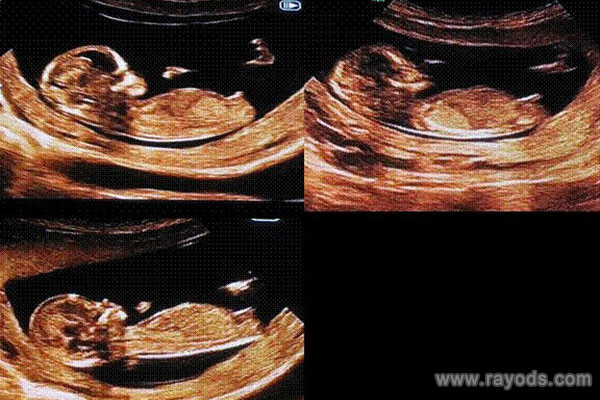

的确,生活中迫切想知晓宝宝性别的家长数不胜数,而通过产检看男女的就最多。产检需要b超成像,运气好的话可以看到宝宝的性别器官,当然,真正的产检医生都会刻意避开这一点。这不,很多人都觉得nt检查的时候可以根据单子上的一些数据和图像等分辨胎儿性别,有过来人透露说如果nt有三个亮点的话就是boy,但在医生看来,nt检查看男女其实并不准确,这是怎么回事呢?

为何nt三个亮点医生说是boy?这个说法其实是网上一些已生宝妈总结出来的,都说这是男孩的生殖特点。因为男孩要发育睾丸和小JJ,而女孩则不会发育这些,因此亮点更好说明是男孩的生殖器。据说如果怀的是女孩的话,双腿间基本都是呈现的线条或者黑杠。据大部分已验证的宝妈来看,三个亮点男孩几率更大,三条线女孩的几率大。

因此,原来越多的人也就觉得nt检查看到胎儿双腿间有三个亮点的话就是男孩。但理论上来说,nt检查的时候是看不到这些类似于胎儿生殖特点的。一般nt检查在11-13周进行,这个孕周胎儿宝宝还太小,外生殖器也还未正式开始发育,因此这个时候看到三个亮点的话要结合其出现的位置进行判断。

如果在这个时候看到三个亮点,且双腿间有明显的凸出,就比如一个圆球样的,那就可判断为男孩了。网上也有医生说了,一般B超双腿间有圆球的说明是男孩的生殖器,其实女孩会有突出,但并不是一个圆球,更多的只是一个鼓包。因此,nt检查的时候这些所谓的生殖器官其实并没有正式发育,看到的亮点也不好判断最终的性别,大家可以等到后面观察B超,这样会更准一些。